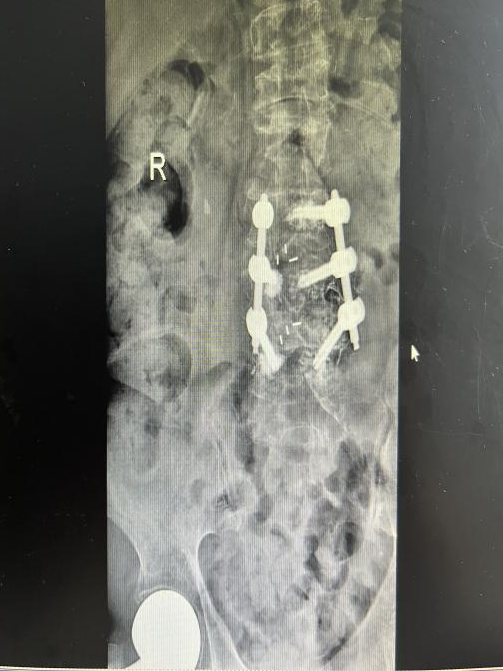

12月17日,贵州航天医院第88次晨读会由我院骨一科主任、副主任医师陈明勇作学术交流,他以“肱骨近端骨折并肩关节脱位的手术治疗”为题,全面讲解了该损伤的手术策略、术中血供保护理念及内侧支撑重建技术等内容,并通过多个典型病例图文资料分享了从损伤机制分析、手术步骤实施到术后随访评估的完整过程与关键细节,为临床处理此类复杂骨折提供了较为全面的技术参考,有助于在手术规划中结合个体情况开展针对性治疗。 贵州航天医院 骨科专家简介 陈明勇 骨一科主任,副主任医师 临床擅长:从事创伤骨科工作约20年,对骨缺损、骨不连、骨肿瘤、肢体畸形等的肢体矫形重建及功能重建,慢性化脓性骨髓炎的根治治疗、糖尿病足的保肢治疗、快速康复理念(ERAS)下的老年骨折的诊治,四肢复杂骨折的诊治,四肢骨折等微创手术治疗具有丰富的临床经验。 2004年毕业于遵义医学院临床专业,曾在中国人民解放军总医院、广西医科大学第一附属医院、上海第六人民医院骨科进修。中国中西医结合学会骨伤科专业委员会横向骨搬移治疗糖尿病足及微血管网再生学组首届委员,遵义市医学会创伤分会常务委员。 瞿 晖 骨科党支部书记,骨二科主任,副主任医师 临床擅长:对骨科的常见病、关节外科、脊柱外科及运动医学疾病的诊治具有丰富的临床经验,熟练掌握骨科手术操作技术。 毕业于遵义医学院临床医学系,2005年前往广州中山大学第一附院骨显微医学部进修学习,2011年前往成都华西医院进修学习,并多次在省内外学习骨科相关知识,是中华医学会骨科分会会员。 赵小锋 中共党员,骨二科副主任,副主任医师 临床擅长:从事骨科临床工作11年,对骨科常见病、多发病诊疗有较为丰富的临床经验,擅长脊柱相关疾病诊断及治疗,尤其是颈、腰、腿疼痛疾病诊断及治疗,擅长胸腰椎骨折微创经皮穿刺内固定术、经皮穿刺椎体成形术、经皮穿刺脊柱内镜下腰椎间盘摘除术、单纯开创腰椎间盘摘除术、腰椎滑脱复位椎间植骨椎融合内固定术、腰椎管狭窄减压融合内固定术及人工髋、膝关节置换术等。 2012年毕业于遵义医学院外科学专业硕士研究生,2019年参加“遵义市115医学人才精英计划”于上海交通大学第一附属医院培训学习,2023年于北京大学第三人民医院脊柱外科进修学习,曾获得遵义市优秀医师荣誉称号。 遵义市手外科第一届委员,遵义市医学会创伤分会第一届委员,遵义市医学会创伤分会第二届委员,贵州省康复医学会第三届脊柱脊髓专业会委员,遵义市医学会烧伤与整形外科学分会委员,发表论文5篇,其中国家级核心期刊1篇,SCI论文1篇,主持市级课题1项并结题,参与市级课题2项。 赵兴东 骨科主任医师 临床擅长:擅长骨科的常见病及各种创伤、四肢骨折创伤修复、骨感染、手足疾病的诊治和手足体表畸形的矫形整复,熟练掌握骨科四肢骨病及创伤的手术操作技术,尤其在四肢关节复杂性损伤、手足外伤、组织缺损创面、难治创面的皮瓣修复方面及平足、高弓足矫形方面及四肢慢性疼痛诊治、康复方面具有丰富的临床经验。 硕士研究生,毕业于遵义医学院临床外科系,2015年前往山东省立医院手足外科进修学习;遵义市医学分会创伤分会第一、二届委员,遵义市手外科医学会第二委届员会常务委员;在省级及省级以上期刊发表文章9篇,参编著作2部,参与主持并完成市级课题1项,参与市级课题2项、省级课题1项。 张艳金 中共党员,骨科副主任医师 临床擅长:从事骨外科工作16年,对复合伤、多发伤的救治、四肢骨干骨折、关节周围骨折、骨肿瘤、骨髓炎等诊治具有丰富的临床经验。 中共党员,硕士研究生,2006年本科毕业于山西医科大学第二临床医学院,2011年研究生毕业于北京军区总医院;在“老年COPD患者合并髋部骨折的诊治”国际合作课题组研究两年,在老年髋部骨折的诊治方面具有丰富的经验,并发表论文6篇;主持遵义市级课题1项,承担遵义医科大学的临床教学工作,获得遵义医科大学优秀带教老师荣誉。编撰有《骨科疾病诊疗精粹》一书,开展2项新技术,编撰地方规范《务川自治县创伤骨科常见疾病诊疗规范》一书。 张俊凯 骨科副主任医师 临床擅长:从事骨科临床工作28年,对创伤骨折、骨感染、骨缺损、骨不连等外科诊治,四肢骨折的微创手术治疗,四肢复杂骨折(如关节内粉碎性骨折、多发骨折等)的损伤控制及手术治疗等具有丰富的临床经验。 1995年毕业于遵义医学院临床专业,2009年前往复旦大学附属医院骨科进修1年。 卢懿明 中共党员,骨科副主任医师 临床擅长:从事骨科工作18年,对创伤骨折、四肢骨折的微创手术治疗、四肢复杂骨折(如关节内粉碎性骨折、多发骨折等)的损伤控制及手术治疗,尤其是髋部骨折的PFNA等微创技术,踝关节骨折、膝关节周围骨折的Mipo微创技术等具有丰富的临床经验,开展了4项新技术,发明6项新型专利技术。 2005年毕业于遵义医学院临床专业,2017年,前往南方医科大学第三附属医院骨科进修半年,回院后运用Mipo技术对骨干骨折及干骺端骨折的治疗技术,同时积极开展骨盆骨折、髋臼骨折腹直肌外侧切口的应用;发表了多篇专业论文,经常参与省内外学术交流会授课,获得医院荣誉称号多个。 邬夏荣 骨科副主任医师 临床擅长:从事骨科工作16年,对四肢复杂骨折、骨肿瘤的诊治,尤其是足踝创伤、慢性踝关节损伤、平足症等诊疗具有丰富的临床经验。 2006年毕业于遵义医科大学临床医学专业,曾在陆军军医大学西南医院进修学习,发表多篇骨科学术论文。 余德怀 中共党员,骨科副主任医师 临床擅长:从事骨科工作10余年,对运动医学、骨关节、脊柱外科常见病、多发病的诊治具有丰富的临床经验。 硕士研究生,2011年毕业于遵义医学院临床医学专业,曾前往遵义医科大学附属医院运动医学专业进修学习;是贵州省医学会运动医学分会青年委员,西部关节镜联盟委员;发表多篇骨科学术论文。 冯 乾 骨科副主任医师 临床擅长:从事骨科工作近20年,熟练掌握骨科多发病及常见病的诊治,尤其对脊柱退变性疾病的诊断及治疗具有丰富的临床经验,主要研究脊柱微创相关治疗方式,能熟练开展椎间孔镜及UBE。 曾前往北京大学第三医院进修学习疼痛及椎间孔镜、首都医科大学友谊医院专业进修脊柱内镜;是贵州省康复医学会第三届脊柱脊髓专业委员会委员;发明专利3项、发表脊柱外科专业论文多篇。 贵州航天医院骨科简介 基本情况 贵州航天医院(原3417医院)骨科组建于1968年,前身是以创伤和断肢(断指)再植闻名于世的上海市第六人民医院骨科,中国断肢(断指)再植的奠基者、中科院院士陈仲伟等专家莅临科室指导医疗和教学,并在70年代开展了贵州省首例断肢(断指)再植手术。组建50余年来,诊治患者已逾百万,挽救了无数的伤病员,成为了保障遵义地区人民群众健康的重要支撑。 经过几代人的不懈努力,今天的骨科,已由创伤骨科发展至骨病、骨肿瘤、骨结核等领域,现有脊柱外科、关节外科、四肢创伤、手足外科四个亚专科,成为了集医疗、教学、科研于一体的综合学科,是贵州省临床重点专科、遵义市临床重点专科、遵义市骨科临床医学中心、遵义市基层骨科专科联盟理事长单位。 科室目前开放床位110张,共有医护人员50余人,副高级以上专家18人,硕士研究生15人。拥有一流骨科医疗设备多台,每年不定期选派优秀技术骨干到全国各大知名医学院校进修、学习、参观、交流,并邀请国内、国外知名专家教授来院进行交流、指导,通过不断引进国内外先进的诊疗技术,科室医疗技术水平稳步提升,为广大人民群众提供了优质的医疗服务。 专科特色 骨一科 (一)骨缺损、骨不连的肢体与功能重建 胫骨横向骨搬移技术治疗糖尿病足: (二)慢性骨髓炎的根治治疗 (三)肢体缺血性疾病如糖尿病足、脉管炎的保肢治疗 (四)皮瓣修复 (五)复杂创伤的治疗 (六)老年髋部骨折及小儿骨折快速手术 老年髋部骨折: 骨二科 (一)胸腰椎骨折微创经皮椎弓根螺钉固定术 (二)老年性骨质疏松性患者腰椎滑脱脊柱内固定术(骨水泥螺钉) (三)V形双通道脊柱内镜技术(VBE)腰椎融合术治疗腰椎退行性疾病 (四)老年性骨质疏松性骨折(PVP/PKP)术 (五)人工髋关节置换术 (六)双侧股骨头坏死人工全髋关节置换 (七)右侧全髋置换术后假体周围骨折翻修 (八)人工膝关节置换术 (九)人工膝关节假体松动翻修 (十)关节镜技术 传统手术切口 关节镜技术切口 诊疗范围 骨一科 1.四肢创伤、矫形。 2.手、足踝外科。 骨二科 end